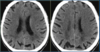

10

Esclerose múltipla